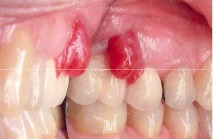

pericornitis

Front

-Erythematous, painful, swollen tissue around the crown of a partially erupted tooth